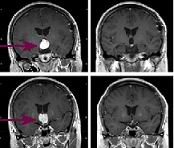

肥胖性生殖無能綜合徵CT圖使下丘腦黃體生成素釋放激素(LHRH)分泌障礙,導致黃體生成素(LH)及卵泡刺激素(FSH)分泌減少,而繼發性腺功能低下,動物實驗證實,累及正中隆起時促性腺激素釋放激素(GnRH)分泌低下,性功能不全可使生殖器萎縮。至於發生肥胖的原因則不是由於缺乏某種垂體激素而是由於下丘腦的損害動物實驗證明:損壞下丘腦的腹內側核及正中隆起,病人的飽感喪失而多食、肥胖。累及腹內側核時,胰島素分泌亢進,致使食慾亢進多食而肥胖。

3.頭部X線攝像及CT、MRI可顯示腫瘤。有顱內疾患的表現者,才符合肥胖性生殖無能綜合徵的診斷標準。

頭部X線攝像,CT、MRI的檢查,可顯示腫瘤。